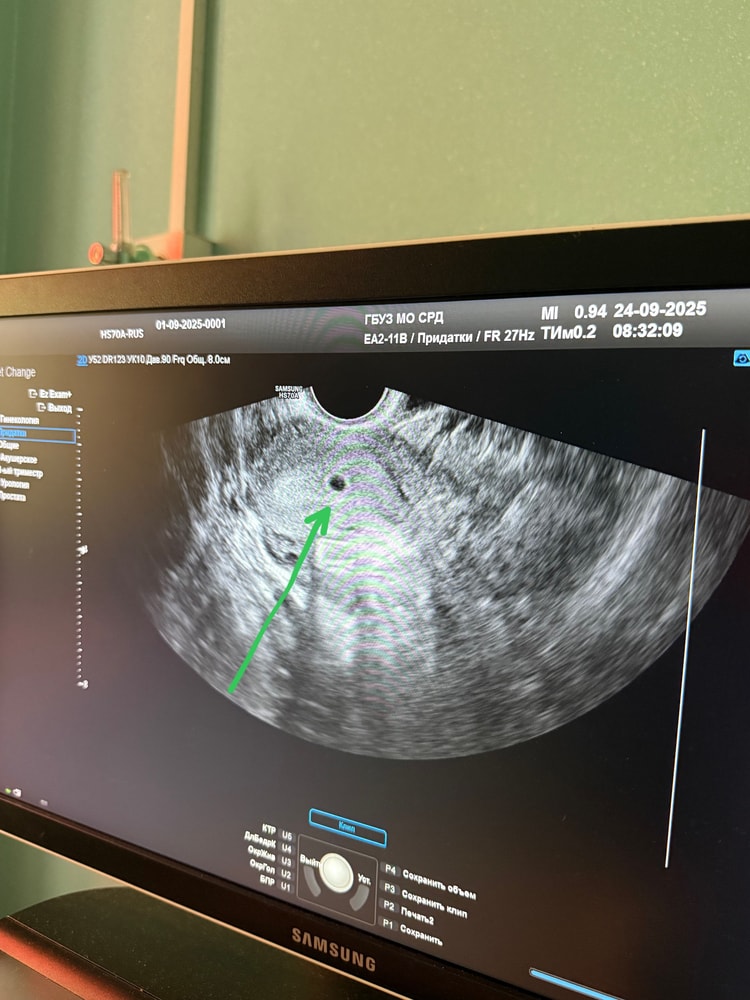

Подтверждение беременности

Хгч от 23.09.25 - 893.5

а сегодня 24.09.25 уже нашли мою бусинку 3,5мм

по узи срок 3-4 недели